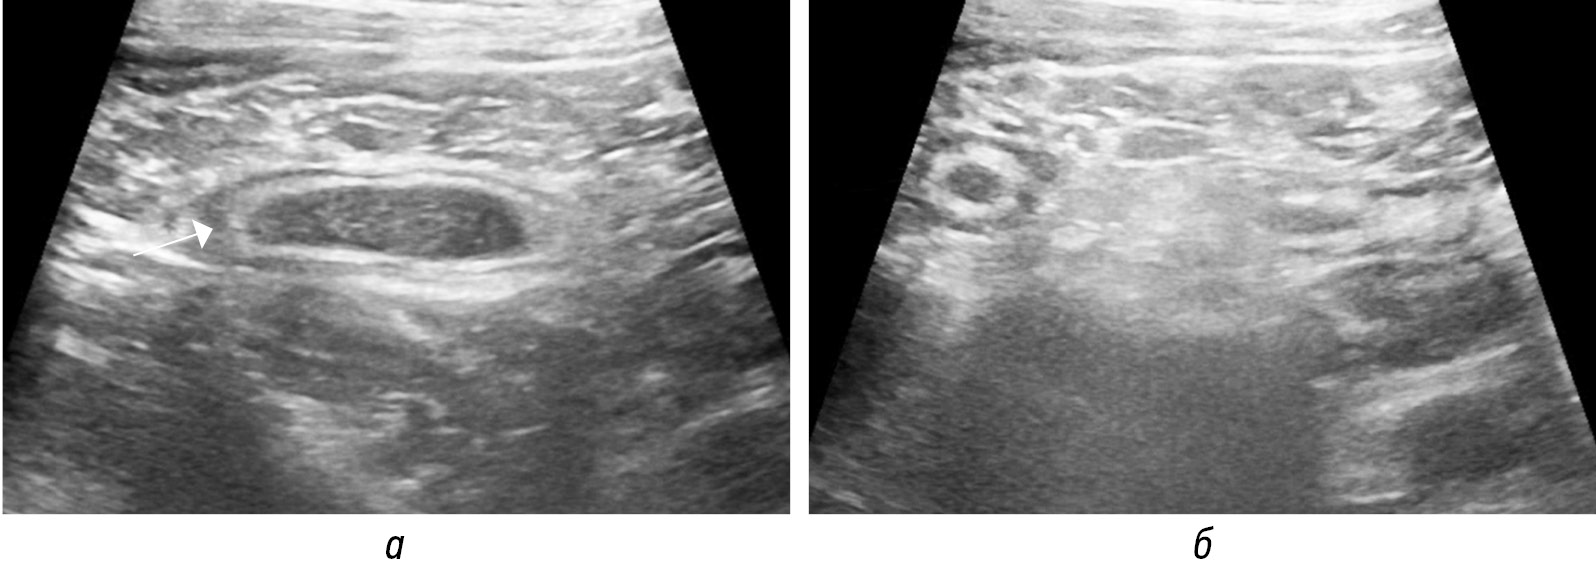

Диаметр аппендикса суммарно представлен содержимым и стенками аппендикса. При нативной КТ не всегда удается дифференцировать стенки от содержимого, необходимо введение контрастного вещества (рис. 2), в то время как при высокочастотном УЗИ возможно дифференцировать слои стенки аппендикса, наиболее информативен срез по короткой оси отростка (рис. 3, а, б). Во всех источниках утолщением стенок аппендикса считается толщина более 2 мм. Только при УЗИ возможно определить несжимаемость при компрессии аппендикса, что является важным признаком острого воспаления [18].

Рис. 3. Сонограммы воспаленного аппендикса (стрелки) в В-режиме по короткой (а) и длинной (б) осям

Fig. 3. Sonograms of the inflamed appendix (arrows) in B-mode on the short axis (а) and on the long axis (б)